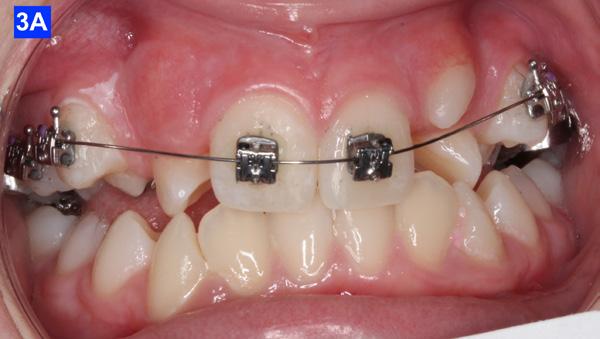

The patient was transferred to our office after 12 months of treatment with her previous clinician. She had a maxillary Hyrax, a mandibular Schwarz appliance and a partially bracketed upper arch with .022 x .028 Passive Self-Ligating (PSL) brackets (Carriere – Ortho organizers). The leveling arch wire was a .018 NiTi. The previous clinician proposed; transverse development, SWA and retention. The patient was already referred to an ENT for the evaluation of her airway. The authors explained to the patient and her mother that we may not be able to accommodate the maxillary cuspids and that odontectomy of two bicuspids may be necessary. We would, however, continue with the expansion protocol to its fullest capacity, utilize Straight Wire Appliances and add TADs to assist with translation of the maxillary cuspids. Class III elastics would be necessary and life-time retention of the dentition

following completion of the treatment. Composite add-ons were considered on maxillary lateral incisors, if required (Figure 3-A, B, C).

4-A, Figure 3A: The patient transferred to our office, frontal view Figure 3B: The patient transferred to our office, maxilla, occlusal view Figure 3C: The patient transferred to our office, mandible, occlusal view Figure 4A: OCS, frontal view Figure 4B: Hyrax, occlusal view Figure 4C: Retraction of maxillary lateral incisors